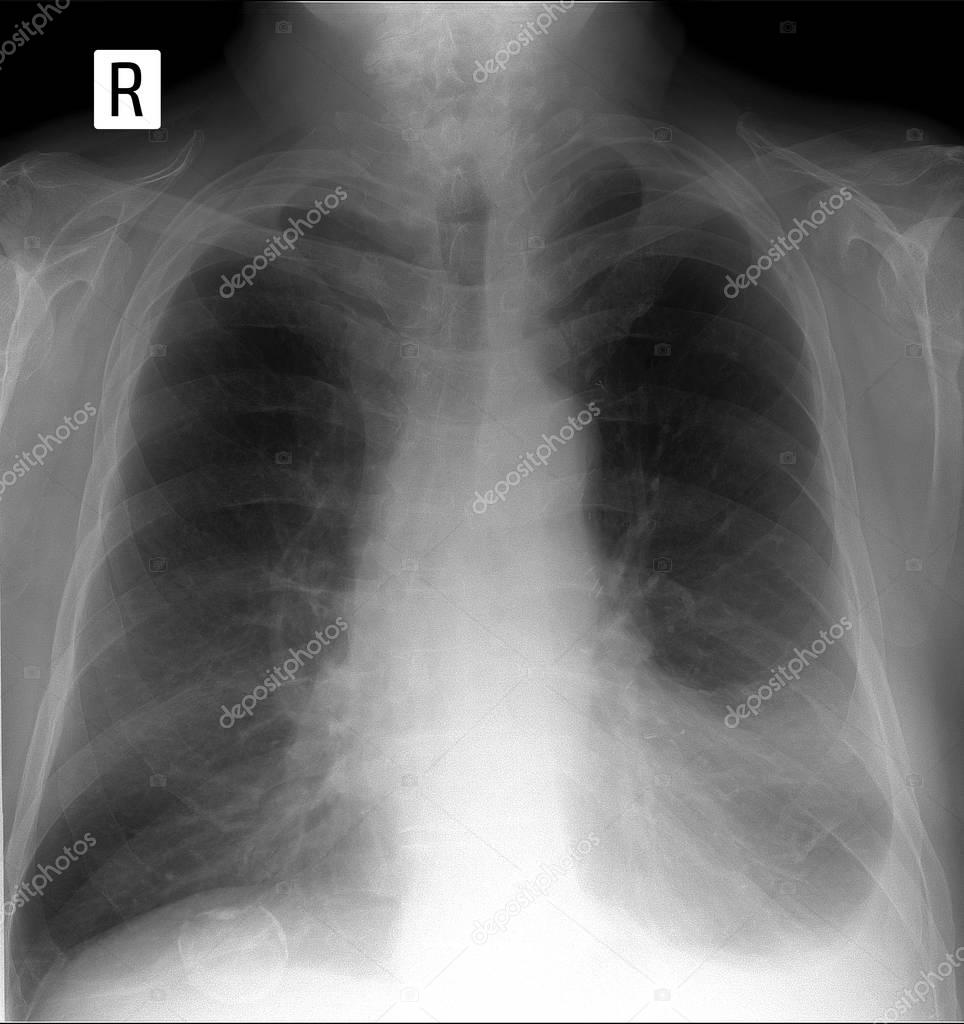

Spots On Chest X Ray Meaning . The phrase ‘lung nodule’ describes a small,. A lung nodule is a small, more dense area of the lung which appears on the image. What does ‘lung nodule’ mean? You may be asked to have a blood test to rule out some of the possible causes of your symptoms, such as a chest infection. The phrase ‘lung nodule’ describes a small, denser area of the lung which appears as a round spot on the image. What does ‘lung nodule’ mean? Lung nodules, in turn, are white specks in that black space, meaning there’s. A pulmonary nodule is an area of tissue that is more dense than normal lung tissue.

Spots On Chest X Ray Meaning A pulmonary nodule is an area of tissue that is more dense than normal lung tissue. A lung nodule is a small, more dense area of the lung which appears on the image. Lung nodules, in turn, are white specks in that black space, meaning there’s. What does ‘lung nodule’ mean? A pulmonary nodule is an area of tissue that is more dense than normal lung tissue. The phrase ‘lung nodule’ describes a small, denser area of the lung which appears as a round spot on the image. What does ‘lung nodule’ mean? You may be asked to have a blood test to rule out some of the possible causes of your symptoms, such as a chest infection. The phrase ‘lung nodule’ describes a small,.